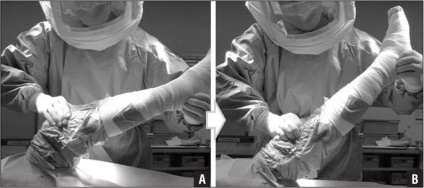

medicii moderni prefera tehnicile care economisesc de intervenție pe un site deschis chirurgicale se efectuează numai atunci când este imposibil să se efectueze procedura de minim invaziva mod. La artroscopie, supraveghere calculator tesut sanatos, practic, nici un prejudiciu, scade riscul de sângerare și de infecție.

- LFK sub practician control. Speranță pentru un miracol imediat după operație nu este necesară, chiar și prima curbă și înmuia piciorul ar trebui sa cu ajutorul unui medic;

Într-adevăr mai bine pentru a obține până cât mai curând posibil, în mod ideal ieși din pat a doua zi după intervenția chirurgicală și au fost luate primii pași.

În cazul în care recuperarea merge bine, de 2-3 zile, puteți începe de mers pe jos, cu un Walker sau cârje. Feedback de la pacienți, în mod competent a luat schema de reabilitare evită complicațiile și pentru a reveni mai repede la viata obisnuita.